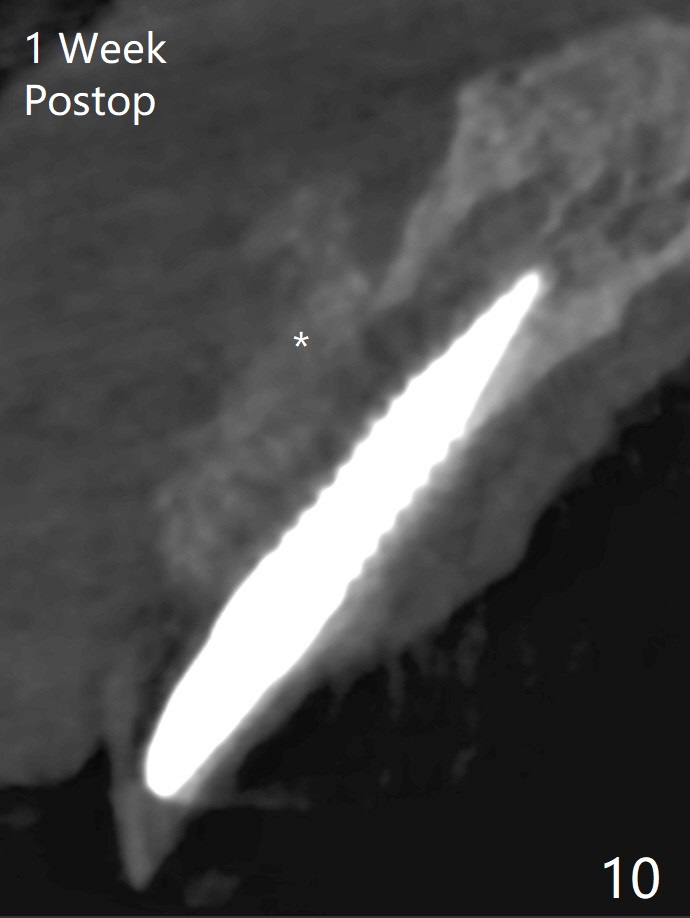

An apical abscess is present when the patient returns for immediate implant at #7 (Fig.1 *); a 2nd challenge is deep bite. After smooth extraction, the apical buccal plate is found to be perforated. Following debridement, a piece of gauze is placed in the apical defect for hemostasis, while osteotomy is initiated palatal (Fig.2). The apical defect seems to be extensive (Fig.3 yellow dashed line). A new trajectory is intended (red arrow) without much success. Before implant placement, bone graft is placed in the apical defect defect area, while a drill (Fig.4 D) is inserted in the finished osteotomy (Fig.5 O). In spite of seemingly large apical defect, the buccal crest bone exists (Fig.4 x). A 3x14(2) mm 1-piece implant is placed with stability; the first round of bone graft is apparently around the apical portion of the implant (Fig.6 *). The coronal end of the implant has to be adjusted several times buccopalatally to accommodate the deep bite. A 2nd round of bone graft following an immediate provisional closes the coronal space of the socket (Fig.7 *). CT will be taken to show the bone graft to repair the buccal plate defect when the patient returns for postop follow-up. In fact the defect is minimal in CT a month ago. The fistula does not disappear 1 week postop, but it is non tender (Fig.8). The patient complains of asymptomatic swelling in the right nostril. CT shows that the large buccal perforation is repaired with large amount of bone graft (Fig.9,10 *). It would be nicer to place the implant slightly more buccal apically (Fig.11 red lines; Fig.12 (preop design)). The buccoapical fistula disappears nearly 1 month postop (Fig.13). The apparently "lifeless" bone graft seems to be harmonious with the surrounding tissue (Fig.14). The periimplant gap reopens with implant mobility nearly 4 months postop (Fig.15), which is related to micro-movement associated with the immediate provisional. The latter is removed. A larger 2-piece implant will be placed in a 2-staged manner if needed (Fig.16). In fact the 3x14 mm straight 1-piece implant (Fig.17) has no mobility when it is retightened, but the trajectory remains buccal. Incision shows that there is no implant thread exposure. A 3x14 mm 15 degree angled 1-piece dummy implant is able to establish the correct trajectory, but there is no occlusal clearance (Fig.18). Micromovement during osteointegration may recreate loosening. Finally using Lindamann bur, the osteotomy is changed so that a 3.5x13 mm 2-piece implant does not need an angled abutment to establish occlusion (Fig.19). There is one palatal thread exposure. Allograft is placed circumferentially, followed by Human Amnion-Chorion Allograft and Collagen Plug. The wound does not heal 8 days postop (Fig.20), as related to the age (79 years old)? The wound appears to heal with a membrane on the surface (Amnion-Chorion one?) 3 weeks postop (Fig.21). The ridge looks wide 3.5 months postop (Fig.22,23). A 4.5x5.5(3) mm appears to be seated incompletely with a gap between the abutment and the implant (Fig.24<). A provisional is fabricated after heavy palatal reduction. Two months later, the provisional fractures. After repositioning the abutment with complete seating and torque (Fig.25), impression is taken. Although the buccal plate is concave, the gingiva remains healthy 10 months post cementation (Fig.26,27).